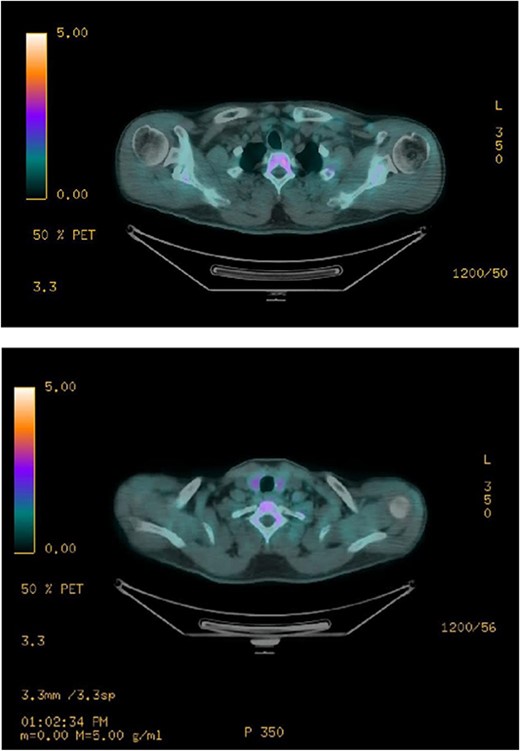

Ultrasound of the neck (Fig. 1), CT and parathyroid sestamibi scan (Fig. 2) failed to localize parathyroid, and all studies showed normal thyroid with no other neck masses or suspicious lymph nodes. Magnetic resonance imaging neck showed no evidence of parathyroid adenoma in the expected typical gland locations or ectopic cervical or upper mediastinum. Therefore, we requested a fluorocholine (FCH) positron emission tomography (PET)/CT (Figs 3 and 4) for localization, which showed normal physiological uptake of the choline in the neck. There was no abnormal focal choline lesion in the thyroid gland or the visualized organs (unremarkable visualized part of the lungs). So, the result was a negative choline scan.